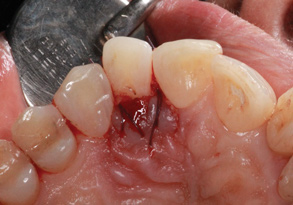

(1.) Pretreatment occlusal view showing crowding and inflamed palatogingival groove of tooth No. 7.

Figure 1

A 45-year-old female patient was referred to our office for the treatment of bleeding gums and sensitivity associated with tooth No. 7. Clinical and radiographic evaluations revealed highly inflamed tissues, easily provoked bleeding, and edematous palatal gingival tissue supporting tooth No. 7 (Figure 1 and Figure 2). Crowding, a widened periodontal ligament, dens in dente, deep probing depths, bleeding on probing, dilacerations, missing papilla, and angular bone loss were also observed, indicating that tooth No. 7 had a poor prognosis. The groove began at the cingulum and formed a deep fold of enamel that extended to the coronal third of the root. This radicular groove disrupted normal periodontal attachment and caused a self-sustaining, progressive localized periodontal pocket to form. The groove also presented a potential pathway for bacterial penetration into deeper parts of the root, which could lead to endodontic involvement if left untreated.6